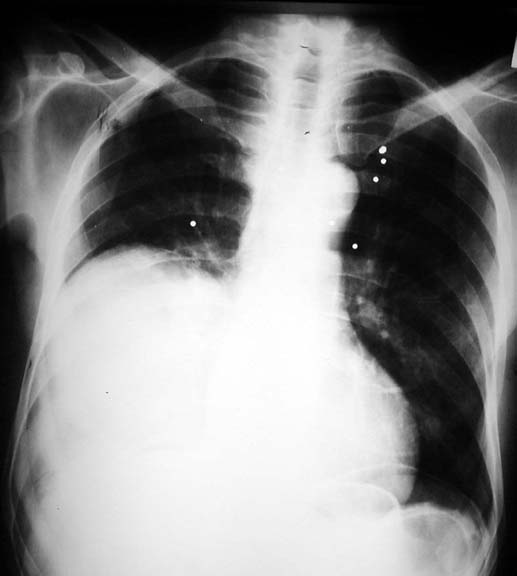

"Elevated Diaphragm"

• Supradiaphragmatic mass

• Can be mistaken for elevated diaphragm

• Pellets